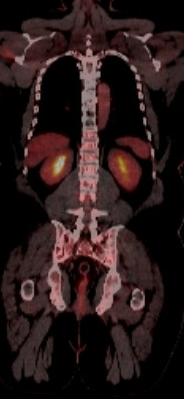

PET/CT scan before stem cell transplant for Clinton Adger

This PET/CT scan shows Clinton Adger's vertebrae before his stem cell transplant.

Multiple myeloma accelerates the normal breakdown of bone tissue. This can cause osteoporosis that weakens the bone as well as soft spots called lytic lesions. Both conditions significantly increase the risk of fracture.

Up to 80% of patients with multiple myeloma develop bone disease, about 5%-10% have spinal cord compression due to lesions, and 47% experience vertebrae compression fractures.